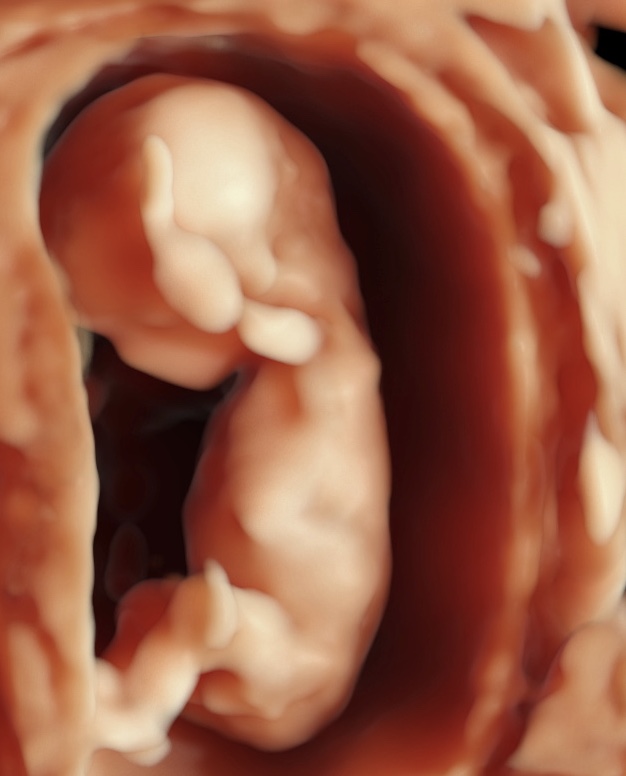

Este es un examen de ultrasonido que se realiza generalmente entre las 4 y 11 semanas de embarazo. Los objetivos de esta exploración son determinar el número de embriones presentes y si el embarazo progresa normalmente dentro del útero.

Esta exploración es útil para las mujeres que experimentan dolor o sangrado en el embarazo y las que han tenido abortos previos o embarazos ectópicos.

INCLUYE:

– Ecografía en HD Live Resolution (5D/7D).

– Estudio Doppler.

– Informe e imágenes impresas en b/n.

– Una foto postal a color.

– Video e Imágenes de la ecografía en MP4 y JPG enviados a su correo electrónico vía nuestra cuenta corporativa en WeTransfer.

– Estacionamiento incluido.

– Explicación de los hallazgos ecográficos.

HASTA LAS 11 SEMANAS.

Este es un examen de ultrasonido que se realiza generalmente entre las 4 y 11 semanas de embarazo. Los objetivos de esta exploración son determinar el número de embriones presentes y si el embarazo progresa normalmente dentro del útero.

Esta exploración es útil para las mujeres que experimentan dolor o sangrado en el embarazo y las que han tenido abortos previos o embarazos ectópicos.

INCLUYE:

– Ecografía en HD Live Resolution (5D/7D).

– Estudio Doppler.

– Informe e imágenes impresas en b/n.

– Una foto postal a color.

– Video e Imágenes de la ecografía en MP4 y JPG enviados a su correo electrónico vía nuestra cuenta corporativa en WeTransfer.

– Estacionamiento incluido.

– Explicación de los hallazgos ecográficos.